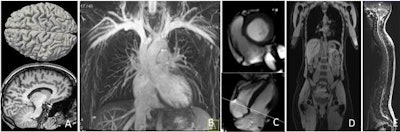

The images show examples of the NAKO whole-body MRI protocol. A: 3D magnetization-prepared rapid acquisition gradient-echo (MP RAGE) sequence of the brain for volumetric reconstructions. B: Plain thoracic angiography. C: Three- and four-chamber views of the heart using 2D cine steady-state free precession (SSFP). D: T1 Dixon sequence over the upper part of the body for fatty tissue differentiation. E: A T2-weighted turbo spin-echo (TSE) scan of the entire spinal column. In addition, the MRI protocol includes, but does not illustrate, resting-state functional MRI and 2D fluid-attenuated inversion-recovery (FLAIR) scans of the brain, modified look-locker inversion recovery (MOLLI) sequence of the heart, 3D proton-density fat-saturated image of the entire hip, a T2 half-Fourier acquisition single-shot turbo spin-echo (HASTE) scan of the lungs, and a multiecho volumetric interpolated breath-hold examination (VIBE) liver scan. Reprinted with permission of RSNA.

In addition to providing a morphological image of the brain (T1-weighted and fluid-attenuated inversion recovery [FLAIR]), the investigation will also include a functional MRI scan. There will also be functional cardiovascular sequences, plain thoracic MR angiography, full-body Dixon sequences, and a T2 half-Fourier acquisition single-shot turbo spin-echo (HASTE) scan of the chest and upper abdomen. Musculoskeletal imaging includes a sagittal T2 scan of the spinal column and high-resolution imaging of the sacroiliac and hip joints.